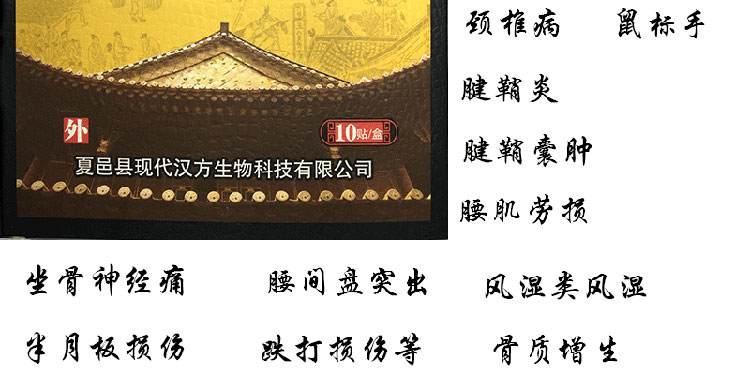

【产品名称】:吕家传冷敷贴